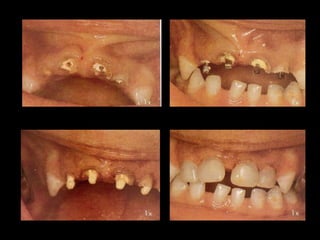

• Dentes

decíduos

com

ampla

destruição

que

sofreram

tratamento

pulpar

e

passar

do

tempo

tornaram‐

se

friáveis

cárie

rampante

ou

hipoplasia

severas

• Casos

de

restaurações

classe

II

aliadas

a

V

Indicações:

• Grandes

fraturas

da

coroa

por

traumaSsmo

anquilosados